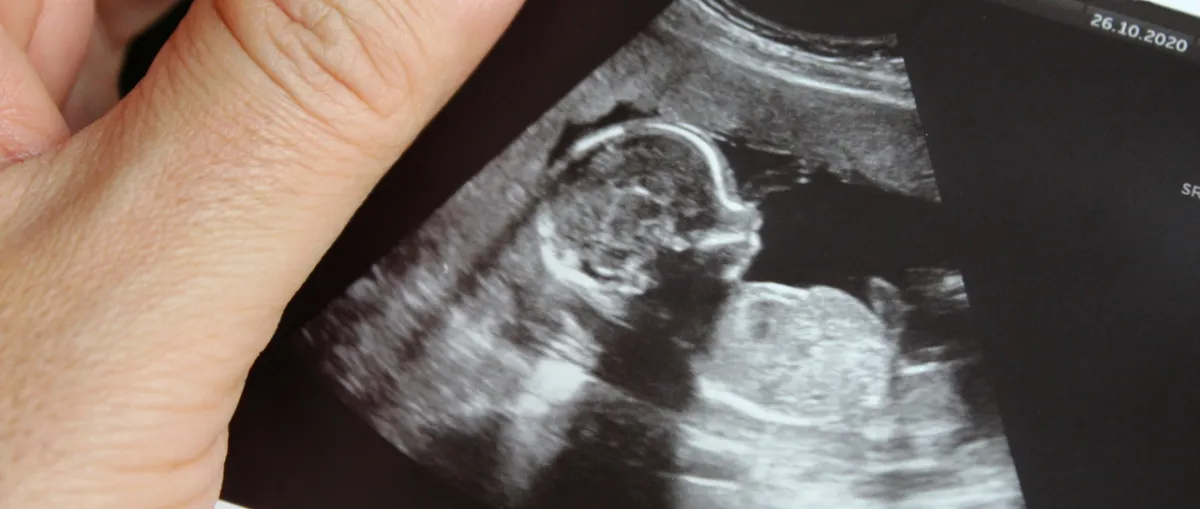

كيف ينمو طفلك في الشهر الخامس؟

1 - قد يصبح طفلك الصغير في الشهر الخامس أكثر نشاطاً هذا الشهر، مع ظهور الركلات والتقلبات أخيراً. 2 - يبدأ في النوم والاستيقاظ على فترات منتظمة، وقد يستيقظ حتى من الضوضاء الخارجية، لذلك لا تتفاجئي إذا شعرت برد فعل بعد سماع صوت مرتفع.

3 - تبدأ بشرة طفلك الصغير في إنتاج كل اللون الزهري وهو عبارة عن طبقة دهنية ملساء تحمي الجلد أثناء وجوده في الكيس الأمنيوسي، وسيساعده عند الولادة.

4 – ينمو الشعر الناعم، الزغب الذي سيختفي قبل الولادة، لكن بعض الأطفال يولدون ببقع صغيرة على أجزاء مختلفة من الجسم.

5 - بحلول نهاية هذا الشهر، قد يمص طفلك إبهامه، حيث يبدأ منعكس المص في التحضير للرضاعة بمجرد ولادته.

6 - ينمو طفلك من حوالي 5 بوصات ووزنه يصبح حوالي 5 أونصات، إلى حوالي 10 بوصات ووزنه حوالي رطل واحد في هذا الشهر. كل هذا يعني أن حجم طفلك مشابهاً لحجم حبة الفلفل أو الموز.